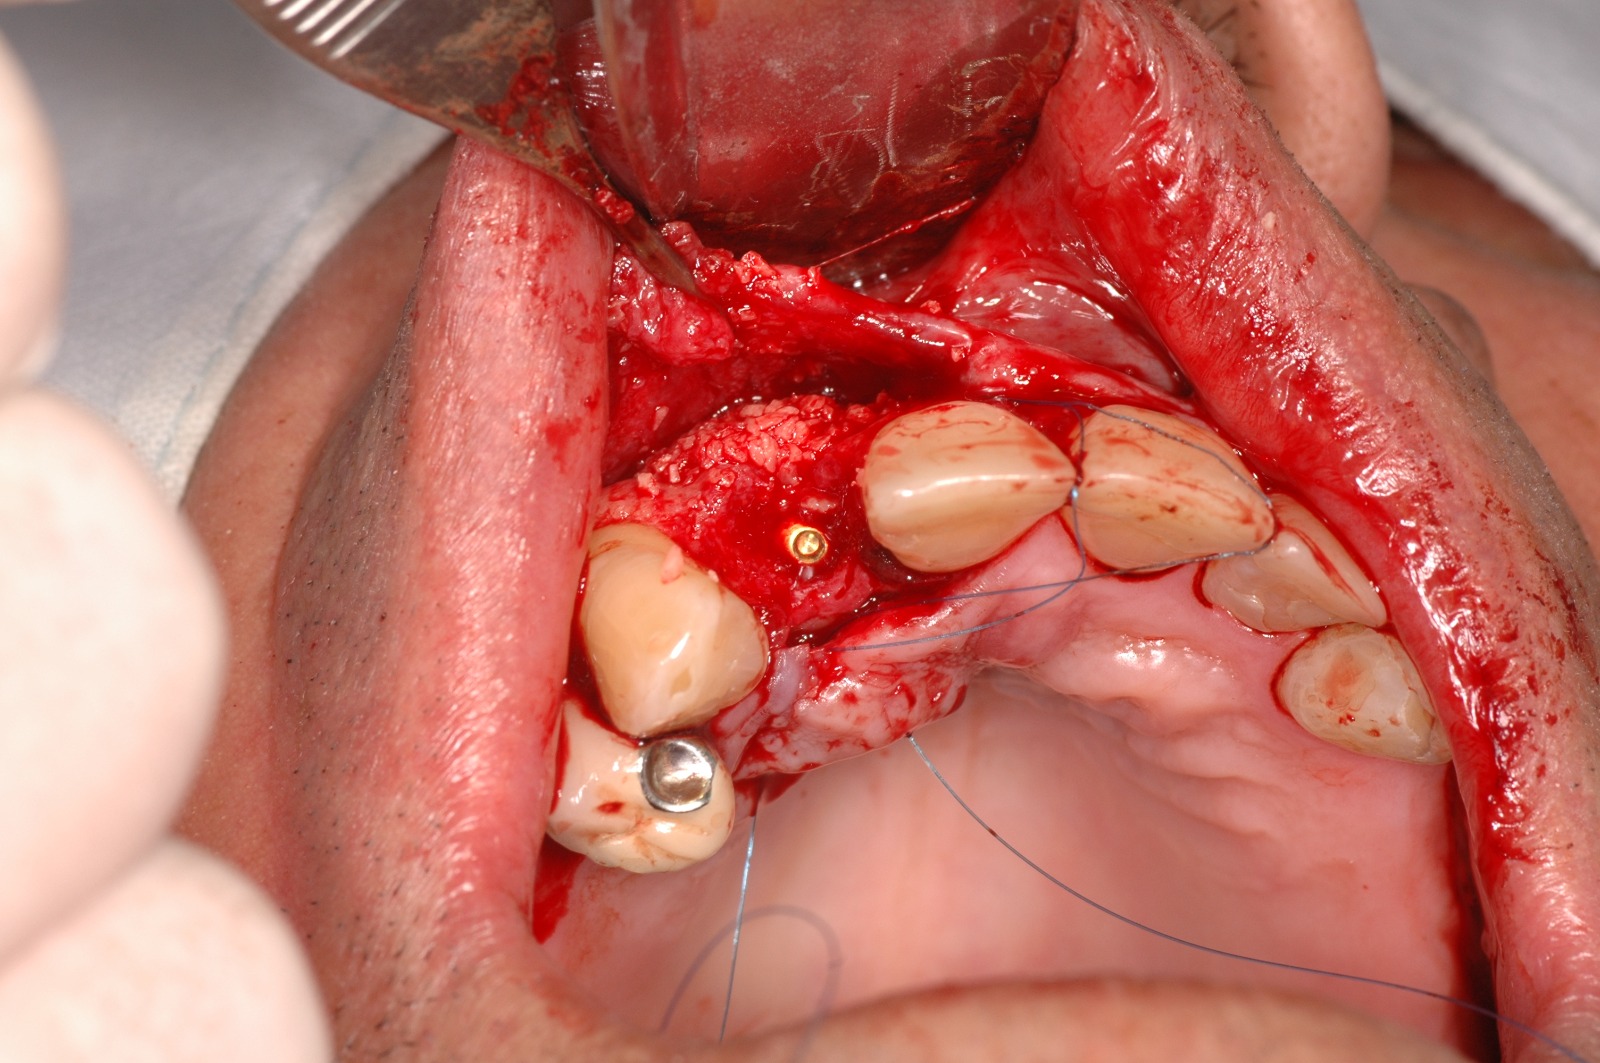

Regeneración ósea guiada

En algunos casos, puede ser necesario realizar un injerto óseo antes o durante la colocación de los implantes dentales. Esto se debe a que la cantidad o calidad del hueso puede no ser suficiente para soportar el implante de manera adecuada.

Casos Clínicos

Observa cómo la ciencia y la tecnología se unen para reconstruir el hueso perdido y devolver la confianza a quien la había perdido